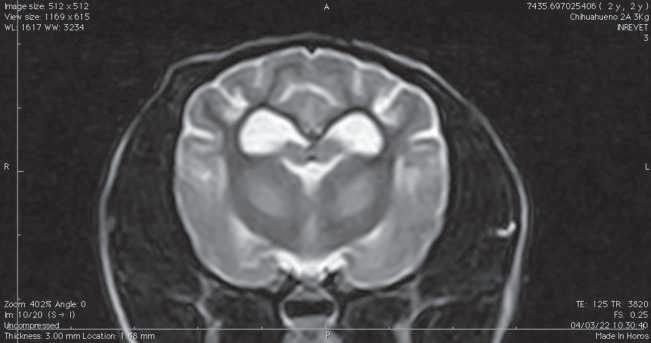

Figura 1. (A y C) Imágenes ponderadas en T2W. (B y D) FLAIR con lesiones hiperintensas en múltiples regiones encefálicas asociados a focos de edema con mayor evidencia en núcleos basales y tálamo (A, B) y lóbulos parietales y temporales (C y D).

A B C D

Figura 2. Imágenes ponderadas en T2W (A, C) y FLAIR (B, D) en las cuales se aprecia una disminución en las lesiones hiperintensas descritas en la figura 1.

Conbasealosresultadosderesonancia magnética (Figura 1), raza y hallazgos neurológicos los pacientes fueron diagnosticados con enfermedad inflamatoria cerebral (Meningoencefalitis de origen desconocido) e iniciaron con una terapia basadaenStee2020,10 conlacombinación decitarabina(Cytosar-U®Pfizer500mg) a dosis de 100/m2 y prednisona a dosis de 1 mg/kg iniciales por 4 semanas (dosis reducción a 36 semanas), para posteriormente evaluar la evolución clínica del paciente y por imagen con las mismas indicaciones de resonancia previamente descritas.

En el presente estudio 5 de 6 pacientes mostraronunamejoracínicasignificativa, enunpaciente(Shih-tzu)elcualingresóen estatus epiléptico no presentó más crisis convulsivas ni se han reportado hasta el momento, el estado mental de los 6 pacientes mejoró de forma significativa, sólounpaciente(Yorkshire)conimágenes por resonancia magnética con herniación subfalcina continuó con giros, los déficits propioceptivos continuaron en 2 de 6 pacientes (Cuadro 3). En las imágenes por resonancia magnética posterior a las 4 semanas iniciado el tratamiento se vio unadisminucióndeledemareportadoque va desde el 85% hasta 50% (Figura 2).